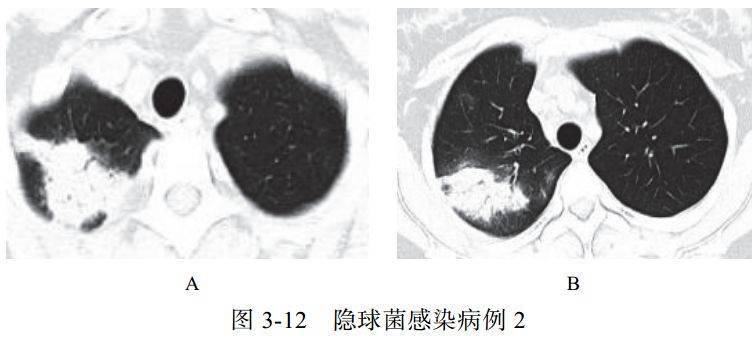

(二)隐球菌感染

肺隐球菌病的病原体为新型隐球菌,此菌为土壤、牛乳、鸽粪和水果等中的腐生菌,感染途径为吸入性。感染人群多见于 40~60岁的成人,临床症状轻,呈亚急性或慢性感染,可侵犯中枢神经系统,表现为慢性脑膜炎、脑膜脑炎或颅内压增高症状

影像学表现:

(1)呈单发或多发斑片 、 类 圆形 或结 节 影, 多位 于 胸膜下(图 3-11)

(2)可出现小空洞、晕征,有时呈炎性肿块改变(图 3-12)

(3)肺门及纵隔淋巴结一般无肿大

(4)病情进展缓慢